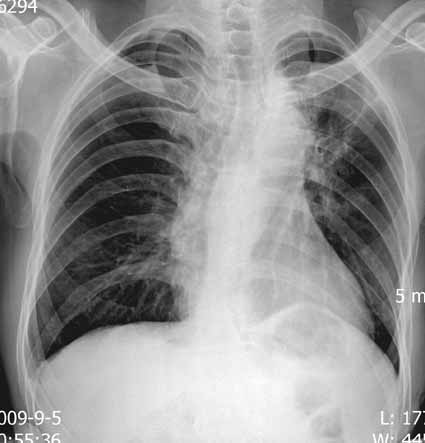

m ,59y,08年12月诊断左侧中央型肺癌,今日复查块影不明显,患者不愿再作ct.

08年cr及ct图像:

今日片: